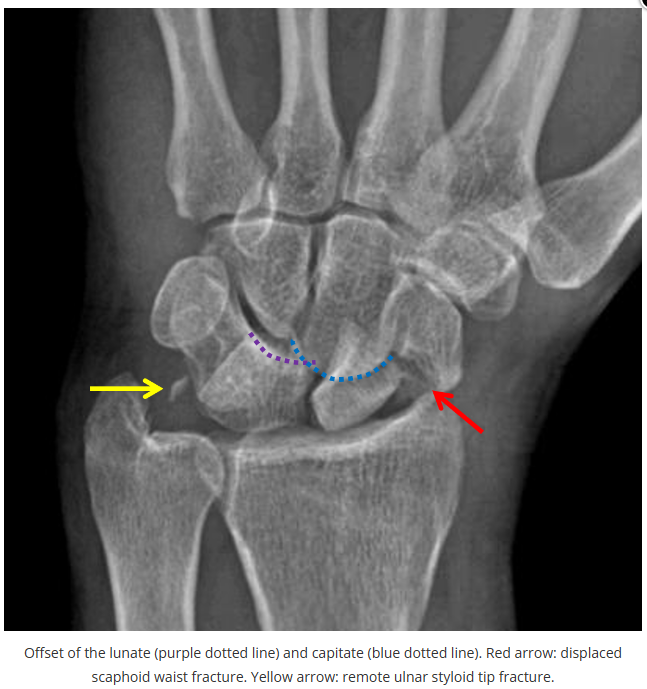

这些腕与手的骨折X线片如果没有标注箭头,你还能识别出来吗?

X线读片是骨科医生的基本功。

今天是腕部与手的X线片。所有X线片都

带有标注和说明

,可以选择长按图片,

自动翻译相关说明